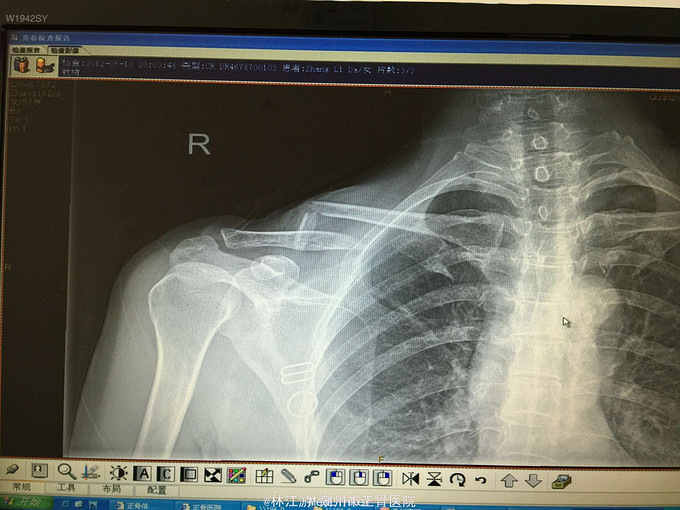

右锁骨粉碎性骨折闭合复位克氏针内固定术

术后三年取内固定物,肢体活动正常